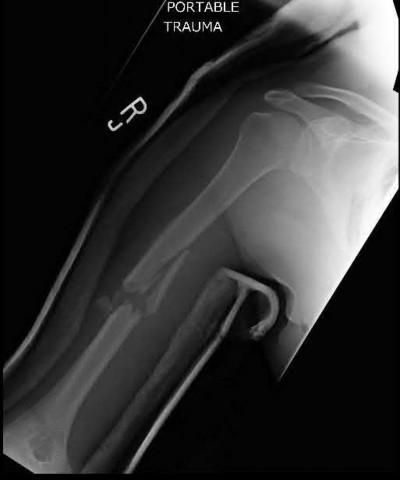

Figure A shows a high velocity shotgun fracture to the left humerus with retained buck fragments. Illustration A shows a similar injury stabilized with external fixation.